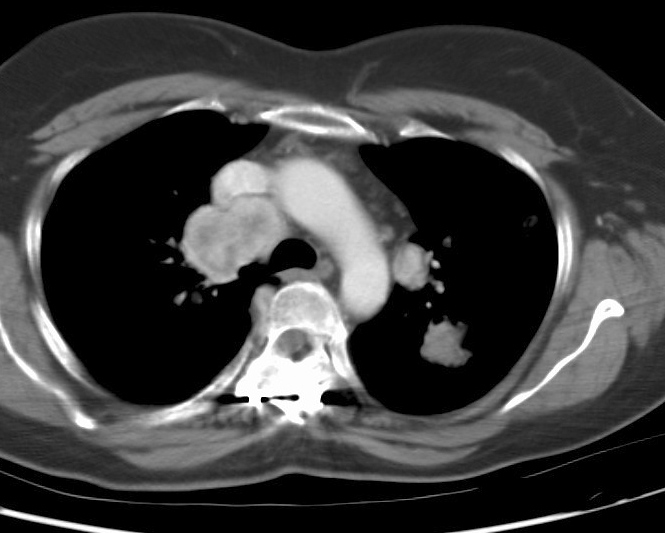

Gallery Lung Cancer Mets Renal cell

Renal cell